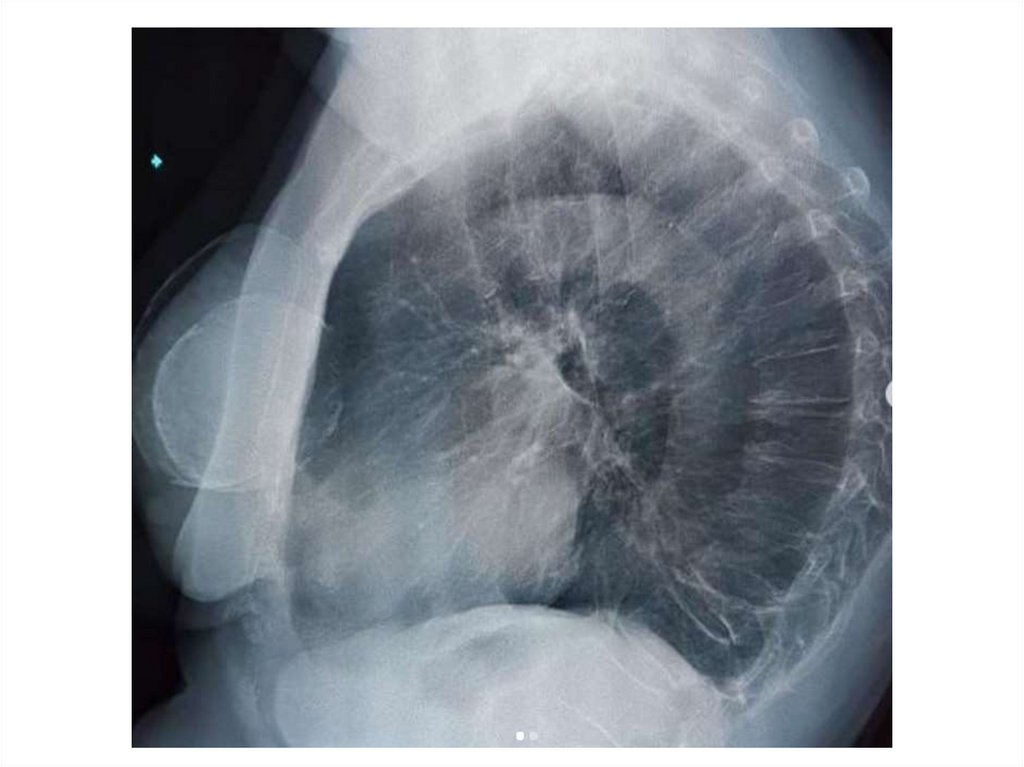

Назовите

• Вид исследования

• Область исследования

• Патологию